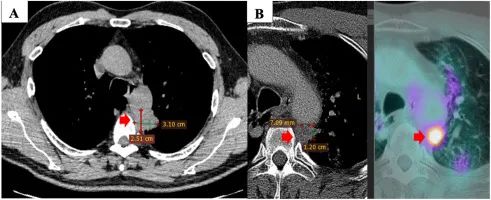

2019 年 5 月,一名 60 歲男性患者,無(wú)吸煙史,有咳嗽、背痛和疲勞癥狀,被診斷為非小細(xì)胞肺癌癌癥。CT 顯示原發(fā)性腫瘤位于左上葉 31×1 mm,侵犯主動(dòng)脈周圍縱隔組織。縱隔內(nèi)出現(xiàn)數(shù)個(gè)淋巴結(jié),最大尺寸為 15×5 mm,右肺上葉有 7 個(gè)淋巴結(jié)顯示,大小分別為 4 mm 和 2 mm。CT 引導(dǎo)下的結(jié)節(jié)和腺癌經(jīng)皮活檢通過組織病理學(xué)檢查(PHE)得到證實(shí),病理分期為 T1N125M55a(IV 期)。腫瘤標(biāo)志物 CA199 輕微升高,CA 和 CEA 之間的邊界正常。分子分析顯示 EGFR 沒有突變。由于病變較大,無(wú)法進(jìn)行手術(shù)。

注:首次診斷時(shí)原發(fā)腫瘤的 CT 掃描檢查(A)。一線治療后原發(fā)腫瘤的 PET / CT 掃描檢查(3 個(gè)周期卡鉑 650mg(AUC5)加紫杉醇 300mg(175mg / m)2)與第三周期的放射治療聯(lián)合)(B)。

從 2019 年 6 月到 2019 年 12 月,患者接受了三個(gè)周期的聯(lián)合放療,其中卡鉑 650mg(AUC5)和紫杉醇 300mg(175mg/m2),第三個(gè)周期。癥狀已部分緩解,臨床和副臨床癥狀均有所改善。患者的正電子發(fā)射斷層掃描(PET)/CT 掃描顯示原發(fā)腫瘤的大小縮小(12×7 mm),腫瘤標(biāo)志物值于 2019 年 12 月恢復(fù)正常。